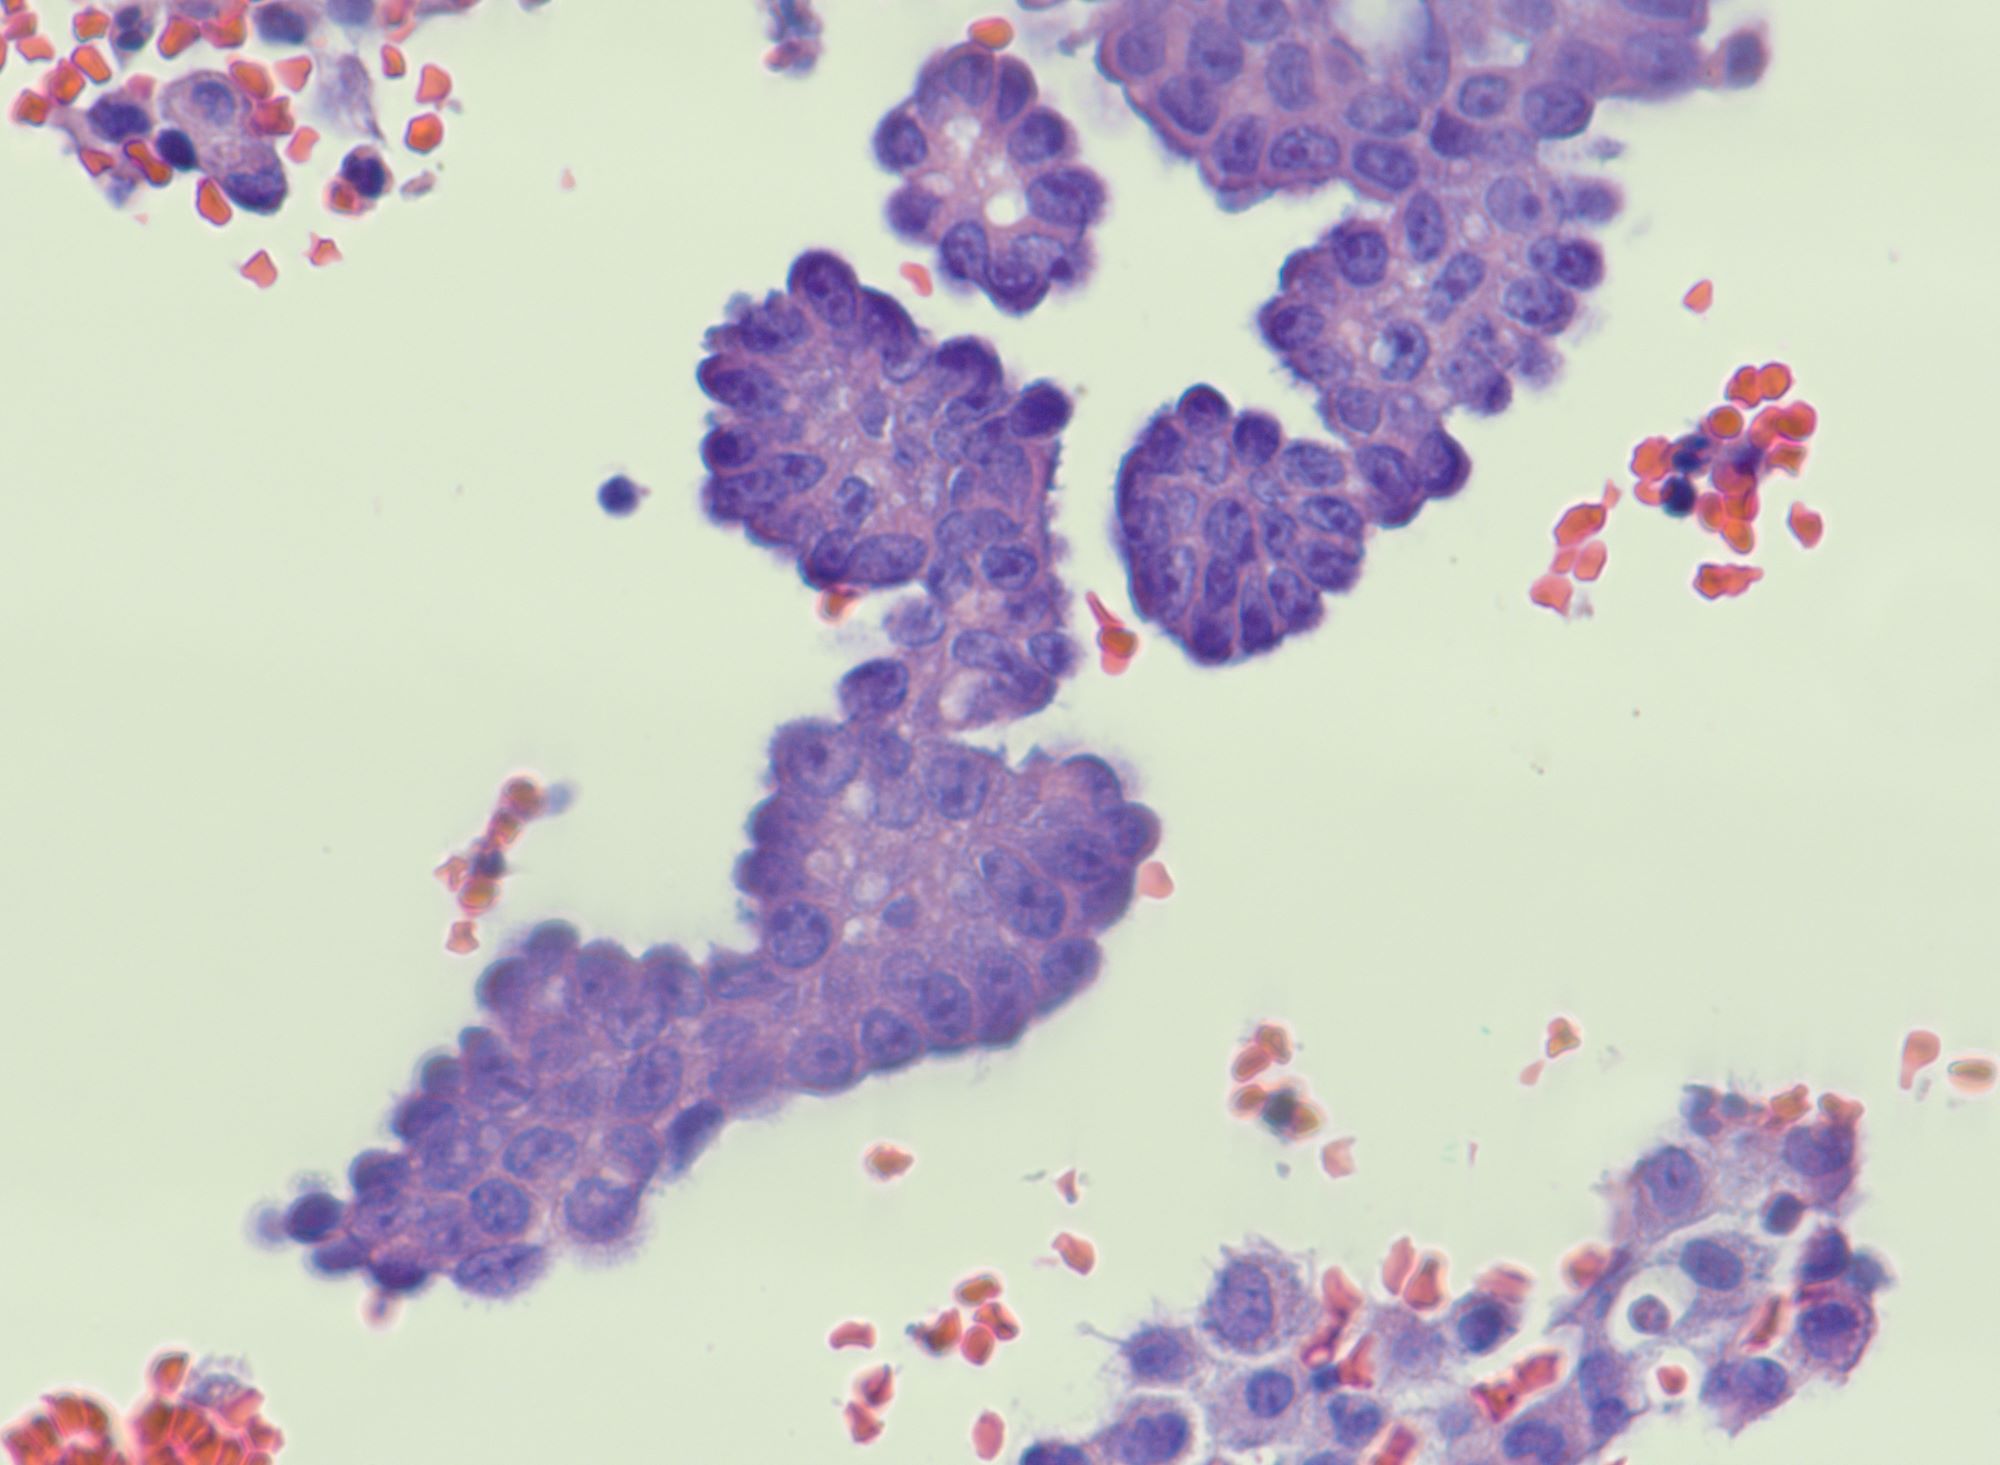

Cytology description

- Malignant glandular cells in clusters and singly

- Moderate amounts of finely vacuolated cytoplasm

- Enlarged hyperchromatic nuclei

- No significant nuclear pleomorphism (< 3x variation in size)

- Prominent nucleoli

Cytology images